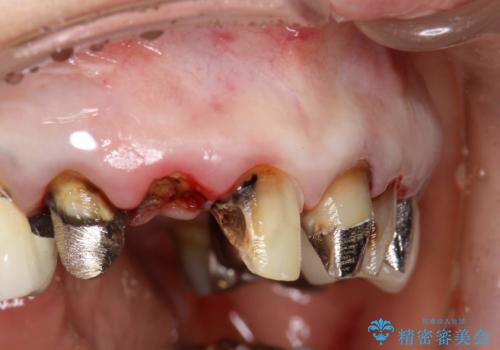

- 歯周外科・再根管治療後、クラウンを製作する。

・虫歯がとりきれていない

・接触部分がガタガタで適合の悪い金属

・全く無菌の努力がされていない根管治療

など、いい加減な治療は「治療」ではなく、むしろ医原性に歯の寿命を短くします。

- 外科手術のため、術後に痛みや腫れ、違和感を伴います